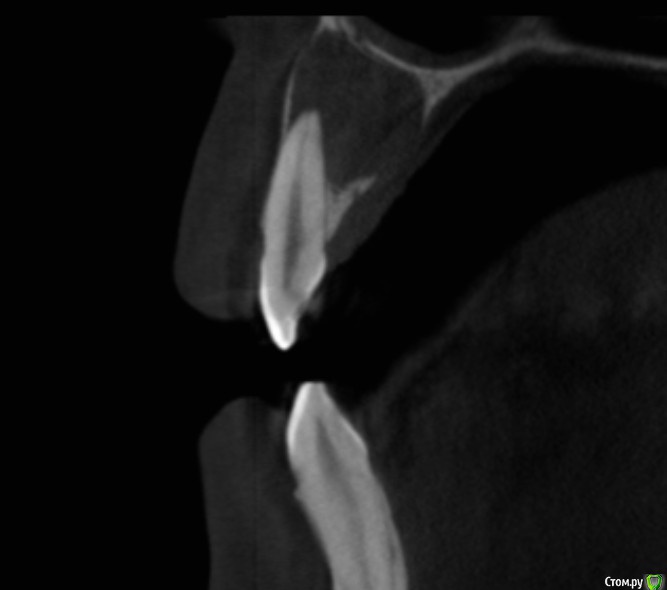

Рустам Опубликовано 17 января, 2016 Поделиться Опубликовано 17 января, 2016 Добрый вечер коллеги! Обратилась пациентка с жалобами на наличие свища в области 22 зуба. Сделали КТ, обширный очаг в области 21, 22. Как считаете, можно попытаться в данной ситуации обойтись консервативным лечением, без хирургии? Ссылка на комментарий

DmitrySH Опубликовано 17 января, 2016 Поделиться Опубликовано 17 января, 2016 Вот честно не вижу заочной необходимости в МТА или IRM. Первичное эндо, констрикция сохранена. И декомпрессия уже самостоятельно наладилась.Я за эндо через кальций до периода стойкой ремиссии. Далее уже закрывать, апексфикация и декомпрессия уже входе лечения по мере необходимости 8 Ссылка на комментарий

Л Ю С Я Опубликовано 18 января, 2016 Поделиться Опубликовано 18 января, 2016 Вот честно не вижу заочной необходимости в МТА или IRM. Первичное эндо, констрикция сохранена. И декомпрессия уже самостоятельно наладилась.Я за эндо через кальций до периода стойкой ремиссии. Далее уже закрывать, апексфикация и декомпрессия уже входе лечения по мере необходимости+1, только выясните витальность 2.1. Судя по кт он уже дохлый. Но не факт Ссылка на комментарий